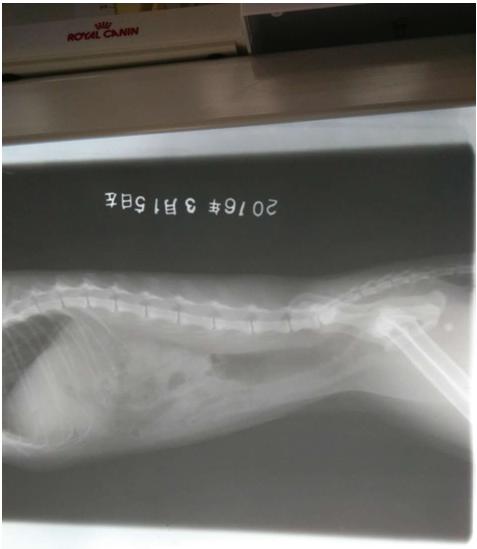

3、在条件允许的情况下,应定期对患猫做X射线、B超复查, 以便了解该病的预后状况,若出现异常情况要及时做出适当的处理。